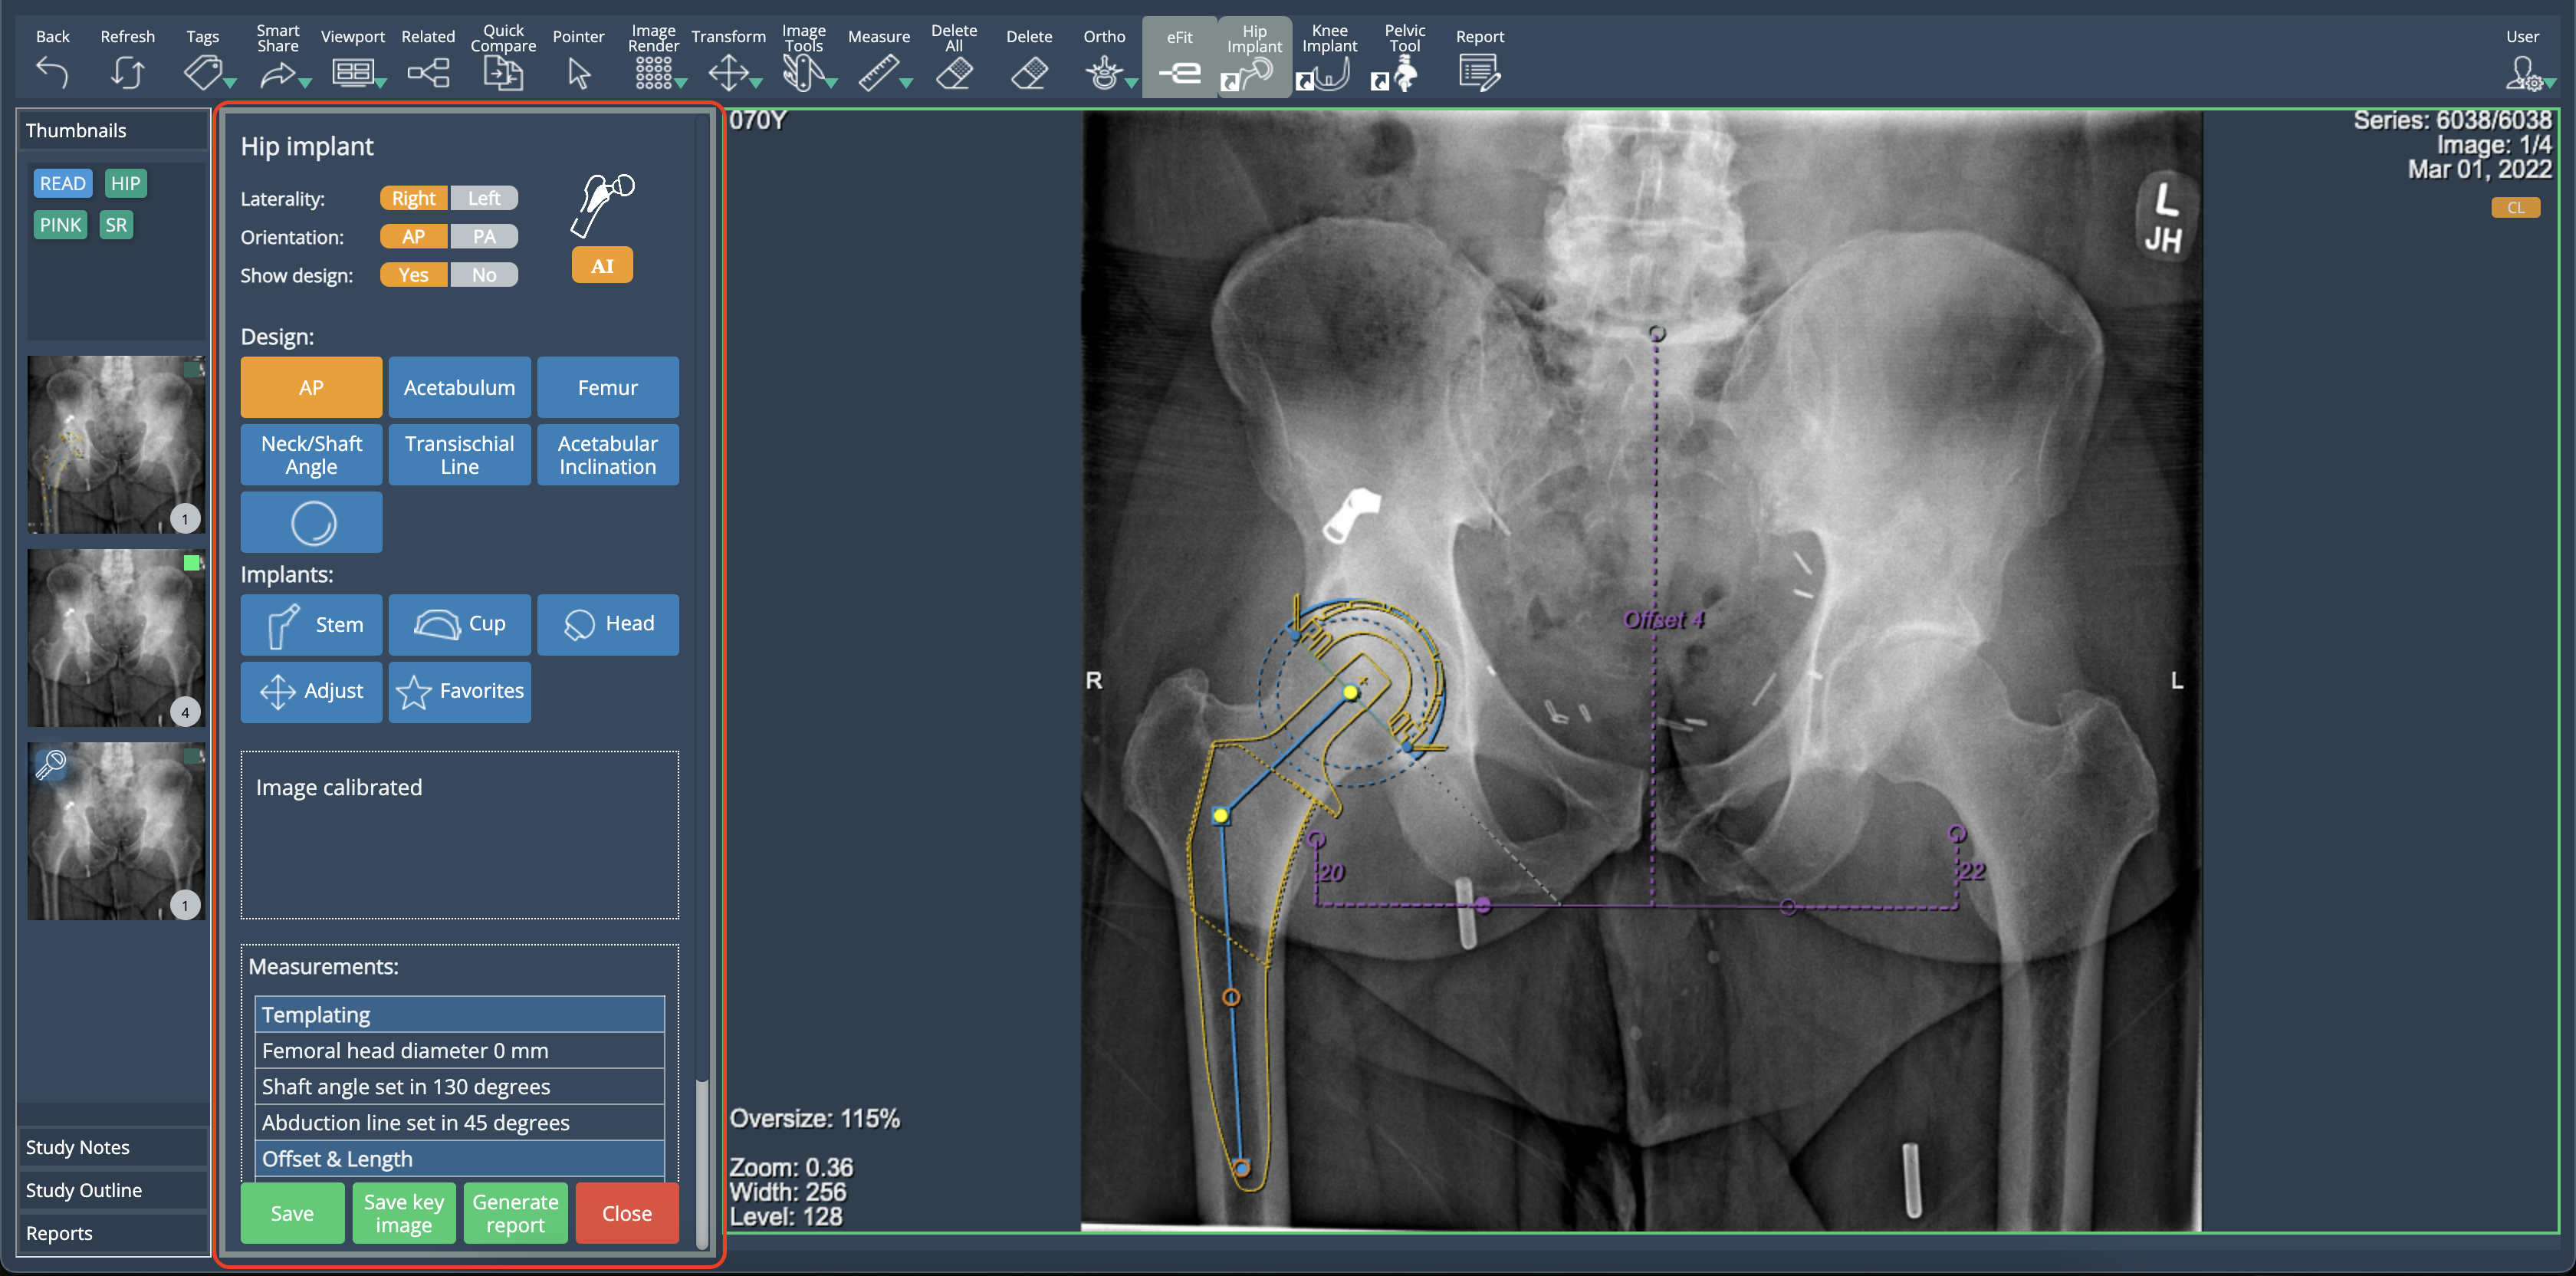

Implant Model Display in eFit

eFit now provides visibility of implant model information. When templating a hip or knee, the implant model number is displayed in the property list of each component. This information is available in the table shown when selecting "Show in Print", ensuring users have quick access to implant details.